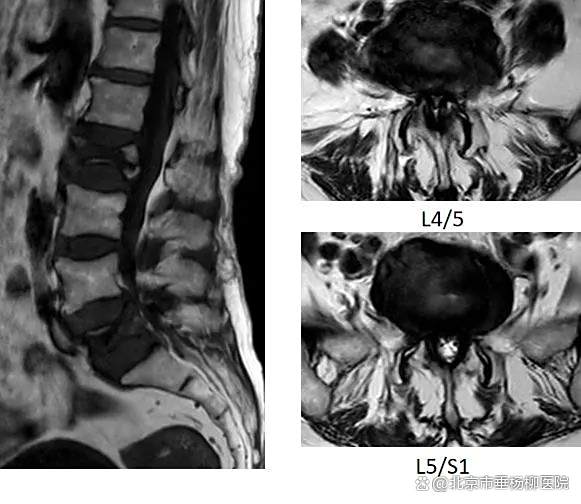

入院后,完善相关检查。经术前MRI显示:患者腰2椎体骨折、腰5椎体骨折、腰椎管重度狭窄。同时,患者还患有高血压、重度骨质疏松。经脊柱外科(骨四科)主任姜树东及科室团队研判,认为患者病灶多、症状重,结合患者高龄,团队评估后计划为患者进行腰2、5椎体成形术+单侧双通道脊柱内镜下椎管减压术(双节段双侧减压)。一次解决患者腰椎问题。

▲术前MRI显示腰2椎体骨折、腰5椎体骨折、腰椎管重度狭窄